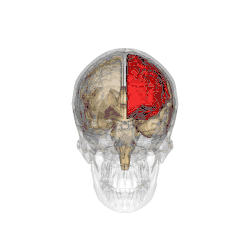

Functional magnetic resonance imaging (fMRI) scans of the brains of subjects exposed to thirty-five hours of sleep deprivation indicate that sleep deprivation is related to increases in prefrontal cortex and parietal lobe activation during tasks that combine verbal learning and arithmetic. This is particularly apparent in the right hemisphere. In non-sleep-deprived people involved in verbal learning and arithmetic tasks, the anterior cingulate cortex and the right prefrontal cortex are active. Following sleep deprivation, there is increased activation of the left inferior frontal gyrus and the bilateral parietal lobes. This information suggests that divided attention tasks require more attentional resources than normally required by a non-sleep-deprived person.[5]

Deficits in cognitive performance due to continuous sleep restriction are not well understood. Studies have looked into physiological arousal of the sleep-deprived brain. Participants, whose total amount of sleep had been restricted by 33% throughout one week, were subjected to reaction time tests. The results of these tests were analyzed using quantitative EEG analysis. The results indicate that the frontal regions of the brain are first to be affected, whereas the parietal regions remain active until the effects of sleep deprivation become more severe, which occurred near the end of the week. EEG and ERP analysis reveals that activation deficits are more apparent in the non-dominant hemisphere—than in the dominant hemisphere.[11]

By contrast, other studies have indicated that the effects of sleep deprivation on cognitive performance, specifically sustained visual attention, are more global and bilateral in nature (as opposed to more lateralized deficit explanations). In a study using the Choice Visual Perception Task, subjects were exposed to stimuli appearing in various locations in visual space. Results indicate that sleep deprivation results in a general decline in visual attention. It is also suggested that the sleep-deprived brain is able to maintain a certain level of cognitive performance during tasks requiring divided attention—by recruiting additional cortical regions that are not normally used for such tasks.[14]